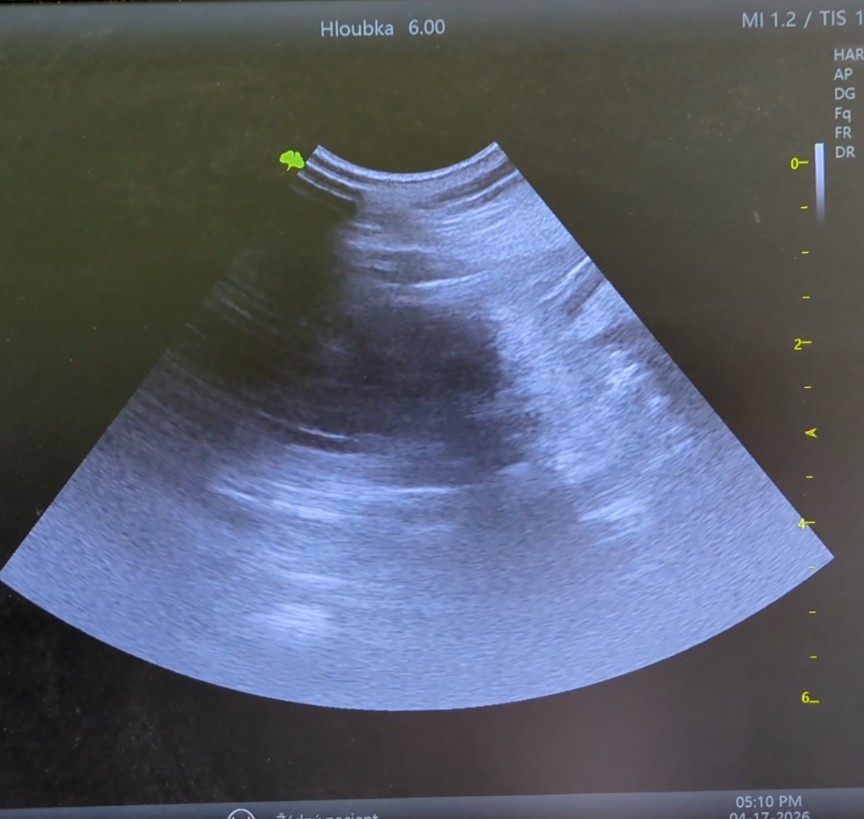

Dnes jsme s Baronkou byli na sonografickém vyšetření, které potvrdilo, že je březí. Budeme se tak těšit na další malé puntíky. Předpokladané narození vrhu je koncem května 2026.